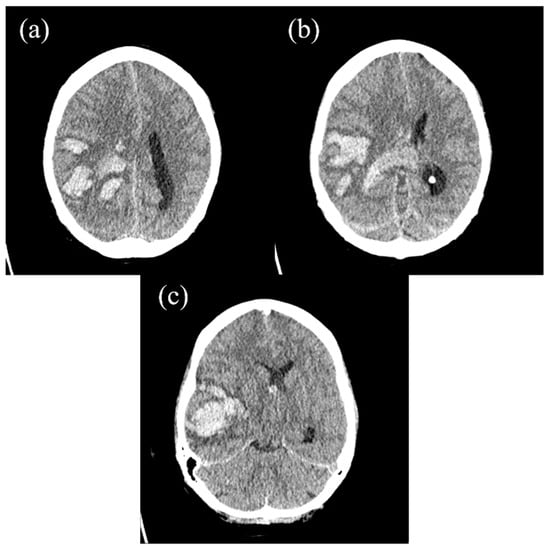

2. The Case Report